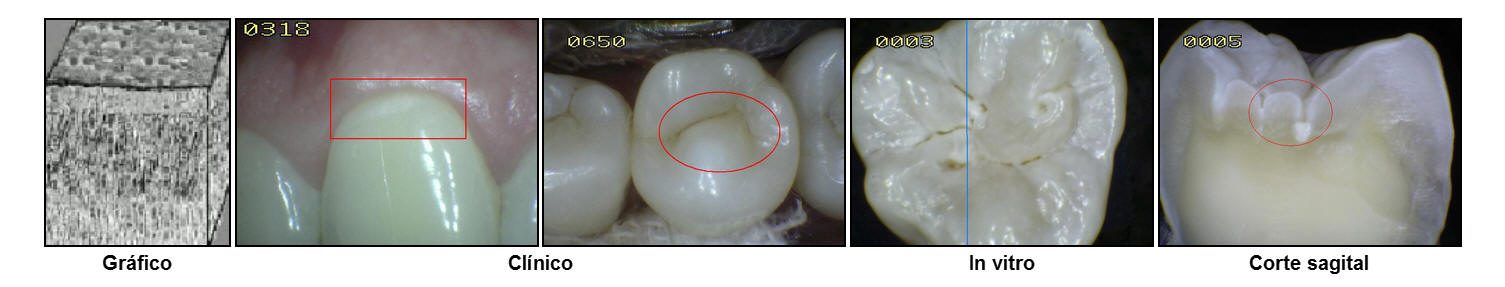

En la imagen

se muestra en color rojo las áreas de estancamiento de la placa

bacteriana en las superficies oclusales, espacios interproximales y los cuellos dentarios. Si la placa

no es

eliminada períodicamente las posibilidad de una lesión cariosa

es alta.

produce una pérdida de integridad superficial y/o cavidad en el esmalte. La fotografía muestra un premolar que fue extraído por motivos ortodóncicos-periodontales. Antes de la extracción el diente fue

cuidadosamente examinado para ver si estaba cariado.

El examen clínico usando espejo y sonda solo detecto

cálculos en el área gingival en las superficies interproximales; no existía

evidencia de deterioro al pasaje del hilo dental entre el

espacio interproximal y el punto de contacto.

Radiografías

de aleta mordible

(bite-wing) fueron tomadas a una exposición normal, y examinadas bajo lente de

aumento; no se encontró ninguna evidencia de caries. .

No

obstante, examinando el diente extraído después de seco y limpio, puede observarse sin dificultad una pequeña región

blanca sobre la superficie proximal (Ovalo en color rojo) Esta es la mancha blanca

que representa la más incipiente evidencia macroscópica de

caries; la superficie del esmalte que cubre esta lesión está

intacta y correctamente mineralizada, sin que pueda detectarse

diferencia al tacto con una sonda de exploración.

La razón por

la que esto es así, es que en la

lesión temprana de esmalte, la desmineralización ocurre

de manera predominante a nivel subsuperficial. La superficie

afectada por esta lesión incipiente aparece intacta y bien mineralizada.

En el gráfico se muestra el

esmalte intacto en la superficie y la sub-superficie. El

aspecto clínico del esmalte es brilloso y translúcido al

secado con aire durante 5 segundos. Se puede observar

pigmentaciones extrínsecas, no consistentes con

desmineralización.